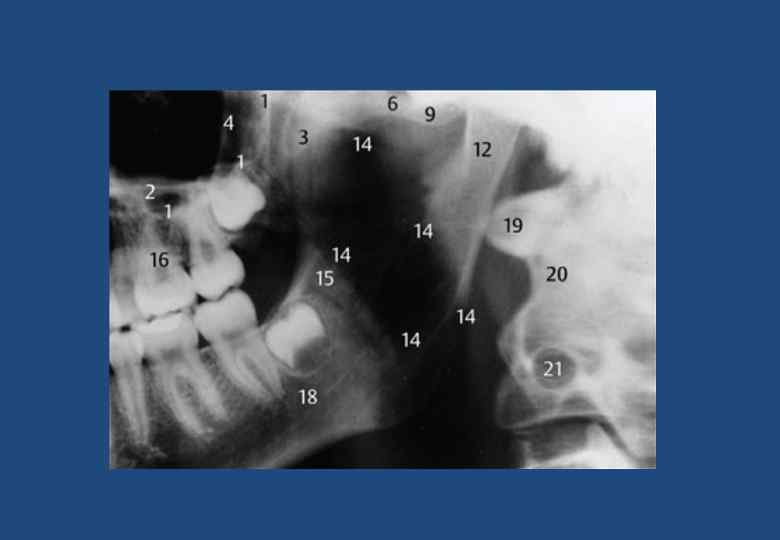

• • • • • • 1. Глазница 2. Шейные отдел позвоночника и зуб второго шейного позвонка 3. Компактный слой вещества в основании противоположной половины челюсти 4. Перегородка носа 5. Нижняя носовая раковина 6. Верхнечелюстная пазуха 7. Передний носовой гребень 8. Горизонтальная пластинка небной кости 9. Боковая стенка полости носа 10. Небная занавеска 11. Крыловидно-небная ямка 12. Тело скуловой кости с безымянной линией 13. Скуловая дуга 14. Компактное вещество тела нижней челюсти 15. Челюстно-подъязычная линия 16. Канал нижней челюсти 17. Подбородочное отверстие канала нижней челюсти 18. Двубрюшная или подбородочная ямка 19. Ушная раковина с отверстием наружного слухового прохода 20. Мыщелковый отросток нижней челюсти 21. Венечный отросток нижней челюсти 22. Шиловидный отросток височной кости 23. Подъязычная кость 24. Основание языка